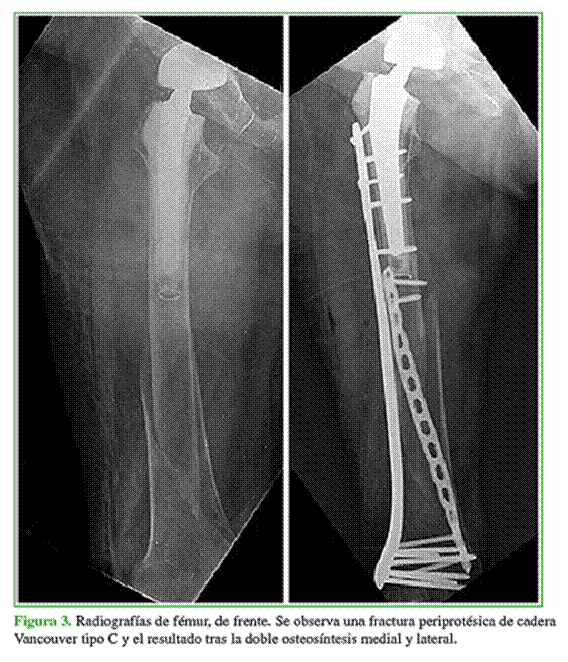

Durante el período de estudio, se incluyó a seis pacientes con una fractura de fémur distal. La serie estaba formada por cuatro (67%) mujeres y dos hombres (33%). Cuatro (67%) tenían una fractura de fémur distal (uno de ellos era un paciente joven con paraplejia desde temprana edad) y dos (33%), una fractura periprotésica Vancouver tipo C (Tabla 1).

En todos los pacientes, se observó la consolidación radiográfica a los seis meses de la cirugía definitiva. Dos pacientes de la muestra tenían, en el momento de la osteosíntesis, defectos metafisarios que fueron resueltos con espaciadores de cemento y antibiótico, por lo que requirieron una nueva intervención con la colocación de injerto de banco. En estos casos, la carga se retrasó seis semanas, momento en el cual se realizó el segundo tiempo quirúrgico que consistió en el retiro del espaciador y el relleno del defecto con injerto óseo cadavérico. Nuevamente, se retrasó la carga seis semanas, y se logró la consolidación en ambos casos. En el resto de los pacientes, se inició un protocolo de carga progresiva que consistió en carga parcial por tres semanas y luego carga completa. Ninguno tuvo una lesión vasculonerviosa asociada (Figuras 3-6).

El puntaje promedio de dolor posoperatorio luego de la consolidación de la fractura fue 3. El paciente con cuadriplejia no fue evaluado en este aspecto (Tabla 2). El seguimiento radiográfico se realizó en el posoperatorio inmediato, a las 3 y 6 semanas, y a los 3, 6, 12, 18 y 24 meses. En la Tabla 3, se describen los resultados funcionales según el puntaje KOOS.6,7 La mediana de seguimiento fue de 24 meses (rango 6-36).